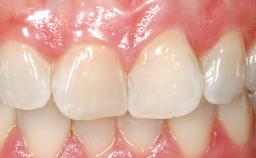

Immediate Flapless Placement of an Implant in a Maxillary Left Central Incisor Site

A 42-year-old female patient was referred to our clinic at the School of Dentistry of the University of São Paulo in November 2004, presenting a deficient restoration in the upper left central incisor. The clinical examination revealed no gingival retraction or any signs of gingival inflammation and, therefore, previous periodontal treatment was not considered. The patient presented a high lip line at full smile and a thin tissue biotype. This combination characterized a high-risk situation from an anatomic point of view, which required careful preoperative planning and cautious surgical execution.

| Provisional Implant-Supported Prosthesis | Prosthodontic margin < 3 mm apical to mucosal margin Prosthodontic margin < 3 mm apical to mucosal margin |

| Soft Tissue Contour and Volume | Ideal |